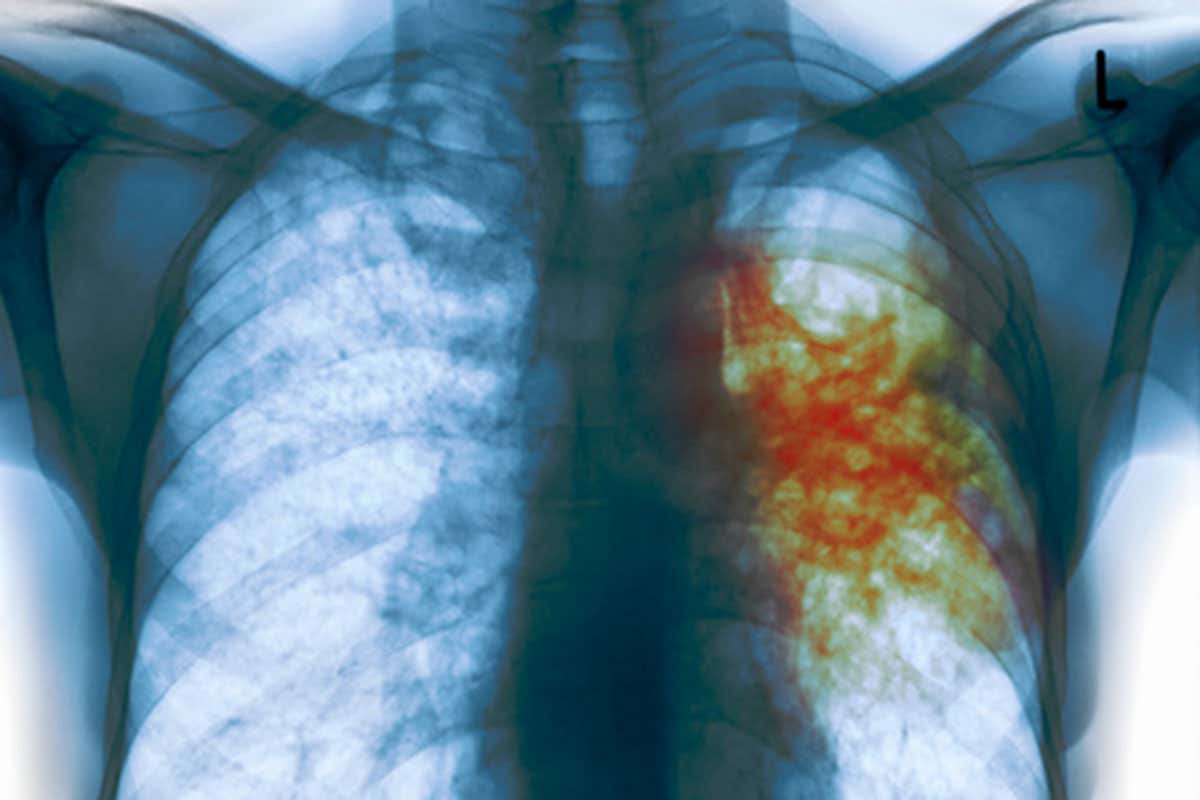

TB Gustoimages/SPL

Once dubbed “Ebola with wings”, tuberculosis resistant to standard antibiotics could finally be on the run.